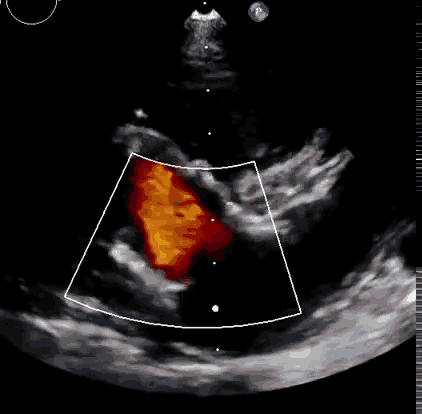

上海中山醫(yī)院葛均波院士、錢菊英院長、周達(dá)新教授、潘文志教授、潘翠珍教授、李偉教授共同完成此次臨床前研究。術(shù)后葛均波院士對Lux-Valve Plus的器械操作性能給予了高度評價,DSA和超聲影像也顯示出在本次研究中Lux-Valve Plus的安全性和有效性俱佳。

本次臨床前研究經(jīng)右側(cè)頸靜脈置入LuX-Valve Plus輸送系統(tǒng)可調(diào)彎鞘管,在DSA及超聲引導(dǎo)下將人工三尖瓣瓣膜植入到原有三尖瓣位置,利用獨(dú)特的錨定技術(shù)將人工瓣膜支架可靠固定在預(yù)定的位置。